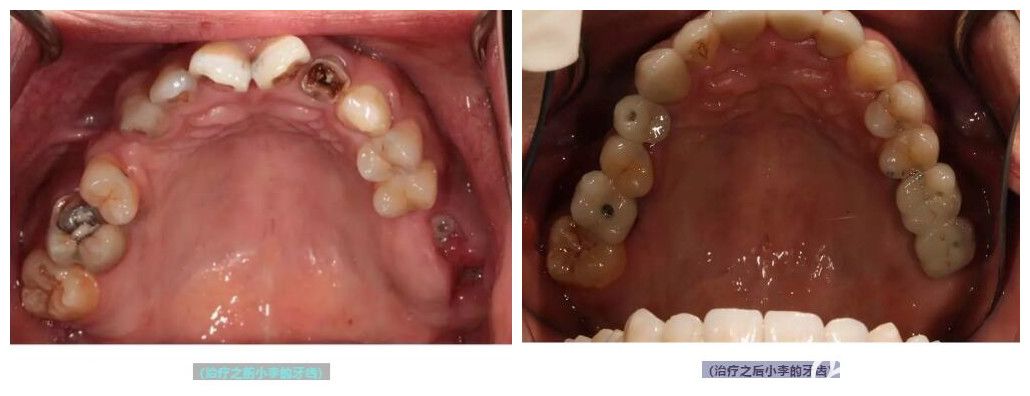

案例:為25歲的小李做即刻種植牙

剛剛二十五歲的小李,牙齒卻比五十二歲的人還差,全口多數(shù)牙齒齲壞,需要種植。

王曉勇為25歲的小李做即刻種植牙案例

在面診過程中被王醫(yī)生的專業(yè)和細(xì)致所折服,就選擇他做了種植牙手術(shù)。

術(shù)后評價(jià):做完種植牙已有一年時間,在術(shù)后的定期復(fù)查中并沒有發(fā)現(xiàn)問題,我現(xiàn)在也和王醫(yī)生成了朋友,經(jīng)常會在微信上聊天,也感謝王醫(yī)生,讓我能夠大塊朵頤,放肆吃喝。